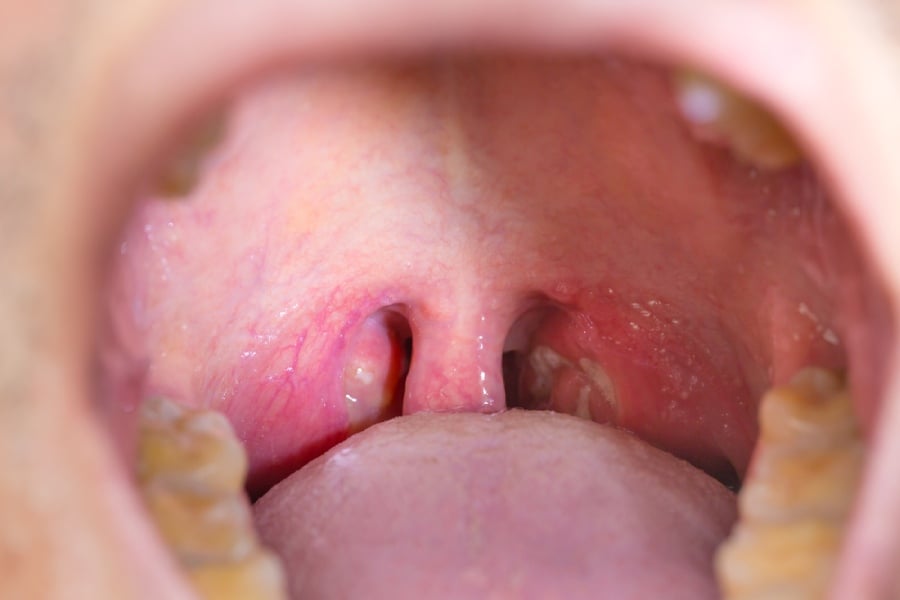

Вирусите и бактериите са първата причина, за която се сещаме, когато става дума за проблемно гърло. Най-често, освен увеличени, сливиците са и зачервени, както и небните дъги. Понякога се наблюдават също различни налепи – белезникави, бели, дори по-тъмни, които с излющването си могат да причинят кръвоизливи.

Въпреки че в повечето случаи не са големи по размер, те стават причина за увеличението на тонзилите. Обичайно се забелязват с просто око и са бели на цвят.